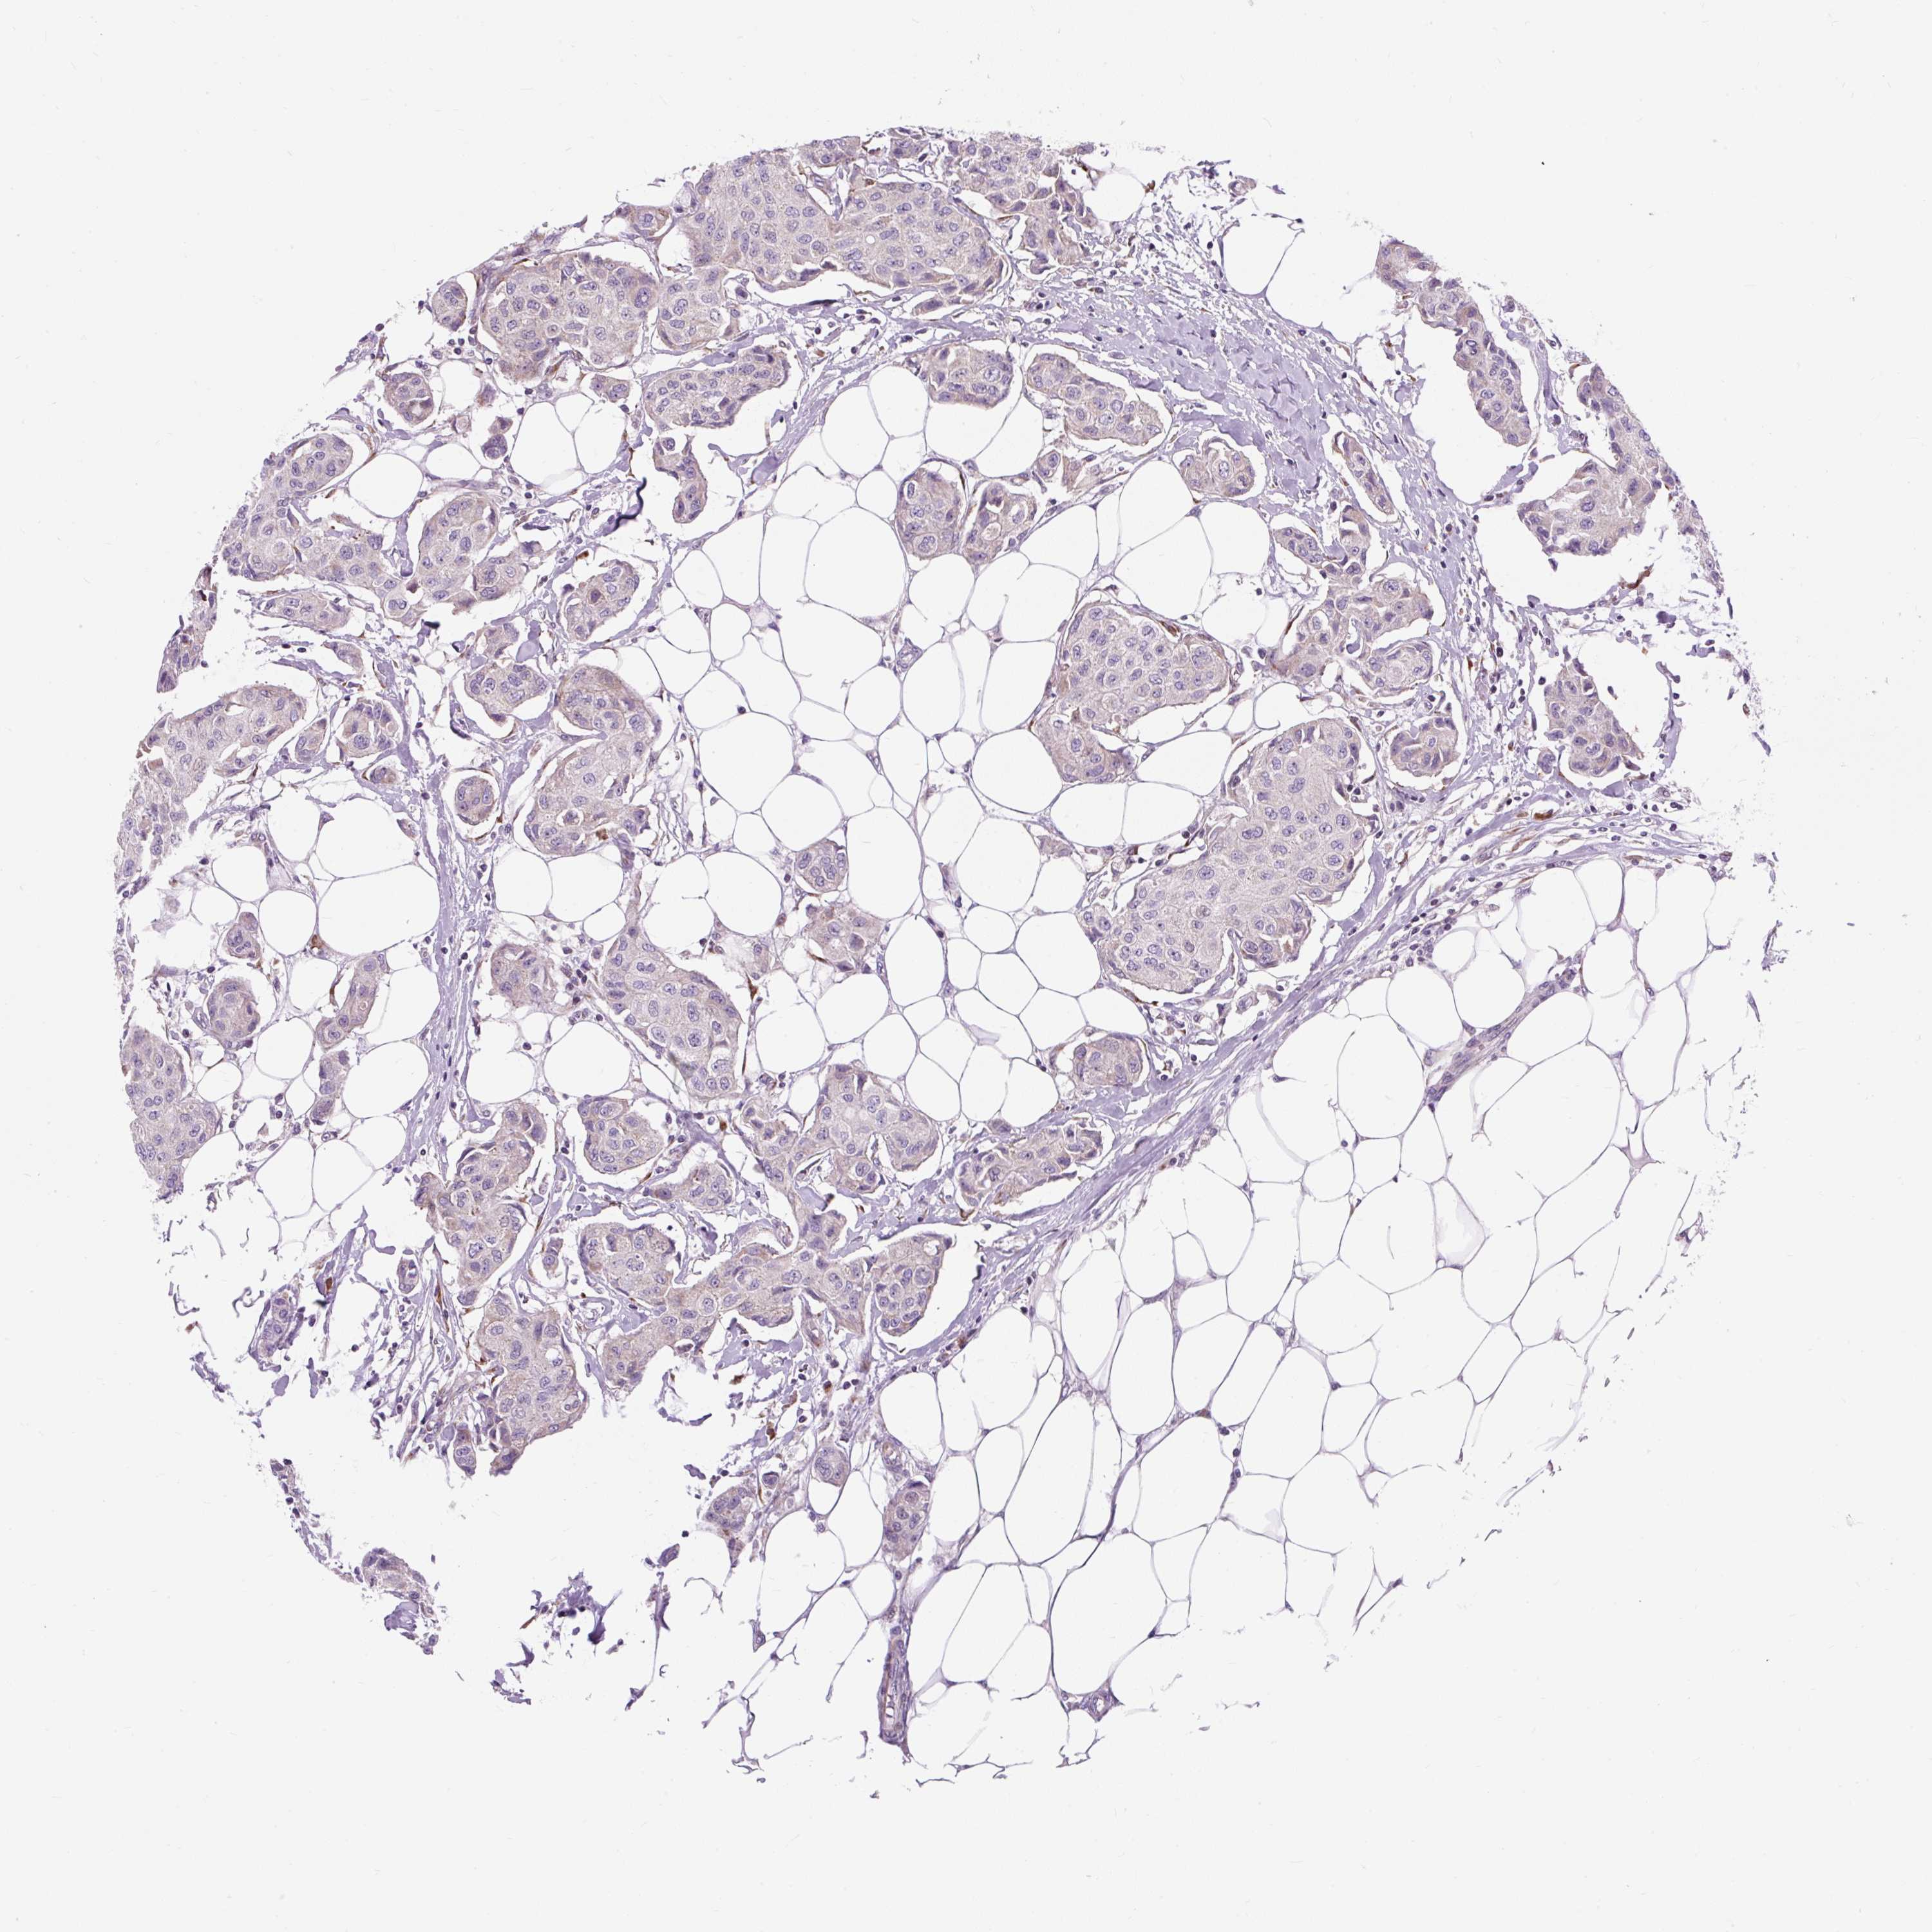

CANCER BREAST CANCER Show tissue menu

BRCA TCGA BRCA VALIDATION PROTEIN EXPRESSION